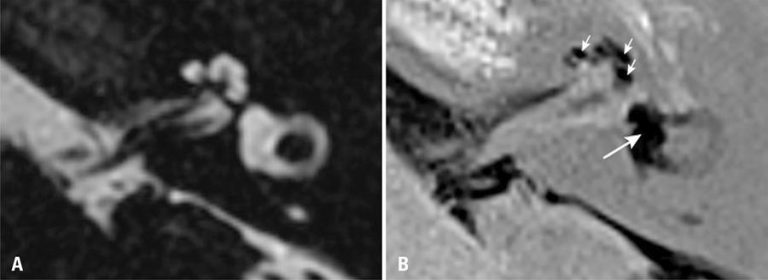

RESUMO Paciente de 34 anos, do sexo feminino, grávida, chega ao pronto-socorro com queixa de dor na fossa ilíaca direita piorando nos últimos 2 dias com suspeita de apendicite aguda. Foram solicitados exames laboratoriais, que estavam dentro dos limites de normalidade para aspectos infecciosos e inflamatórios. Exame de imagem também foi solicitado, sendo a ultrassonografia o método de escolha, que revelou gravidez em curso sem alterações e espessura da parede do apêndice sem sinais inflamatórios. Ainda com suspeita de apendicite […]